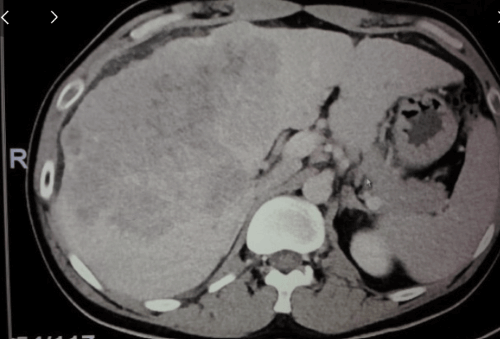

종양이 매우 크고 전이도 있고, 또 혈관 침범도 있는 전형적인 진행성 간암에서 표준 치료는 이 면역 관문 억제제, 면역 항암제를 쓰는 것입니다.

종양이 클수록 또 전이가 많이 있을수록 혈관 침범의 정도가 심할수록 치료 효과가 떨어지는 건 맞는데, 굉장히 심한 환자에서도 효과가 확실하게 나타나는 분들은 종양이 완전히 사라지는 걸 볼 수 있습니다.

이 임상 시험을 통해서 이 간암의 면역 관문 억제제 효과를 봤더니, 완전 반응이라고 말씀드렸잖아요. 이 영상 검사를 했을 때, 암이 안 보이는 그런 완전 반응이 8% 나타났습니다.

그러니까 100명을 치료하면 한 여덟 명 정도에서 진행성 간암에 대한 완전 반응이 나타난다는 거다. 예전하고 비교해선 굉장히 높은 수치입니다,

이 완전 반응이 나타나지 않는다고 하더라도요, 부분 반응이라는 게 있습니다. 그러니까 완전히 없어지지 않더라도 크기가 유의하게 줄어드는 거죠.

암의 크기가 줄어드는 걸, 부분 반응이라고 하는데, 22%에서 그런 부분 반응을 기대할 수 있다. 그러니까 완전 반응하고 부분 반응을 합치면... 30%.

그래서 100명을 치료하면 진행성 간암 100명을 약으로 치료하면 한 30% 정도에서는 거의 없어지던, 아니면 유의하게 줄어든 것을 기대할 수 있다. 이것이 이제 간암 치료의 굉장한 발전이라고 얘기할 수가 있겠습니다.